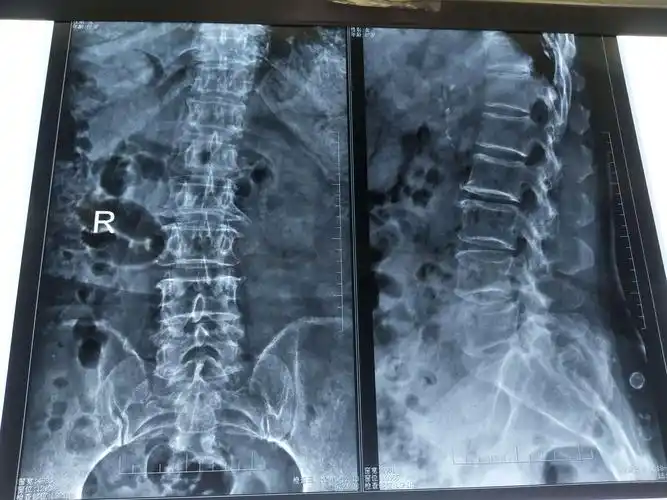

腰椎平片示:腰椎骨质增生